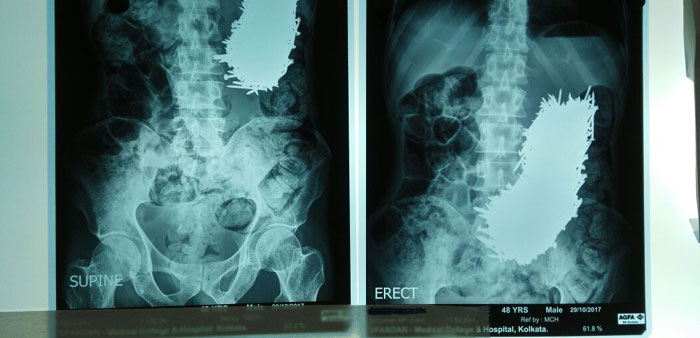

तर मंडळी, ‘कलकत्ता मेडिकल कॉलेज अँड हॉस्पिटल’ मध्ये एक माणूस आला. त्याच्या पोटाच्या वरच्या भागात दुखत असल्याची त्याची तक्रार होती. डॉक्टरांनी तपासणी केली, एक्स-रे काढला आणि मग त्यांना दिसलं की या माणसाच्या पोटात तर चक्क खिळे आहेत.

सर्व खिळे बाहेर काढल्या नंतर त्यांची संख्या तब्बल ६३९ होती. प्रत्येक खिळा हा दोन ते अडीच इंच लांबीचा होता. तुम्ही फोटो मध्ये हे पाहू शकता.